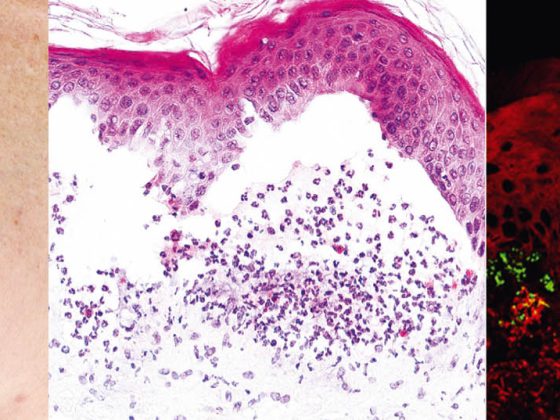

Bullöse Autoimmundermatosen stellen eine heterogene Gruppe von seltenen, teils schweren Autoimmunerkrankungen dar, zu welchen die Pemphigus- und Pemphigoid-Erkrankungen, die Epidermolysis bullosa acquisita und die Dermatitis herpetiformis Duhring zählen. Gemeinsames Charakteristikum der bullösen Autoimmundermatosen – mit Ausnahme des M. Duhring – sind Autoantikörper, welche gegen Strukturproteine der Haut und Schleimhäute gerichtet und für einen Verlust der kutanen Integrität verantwortlich sind [1].